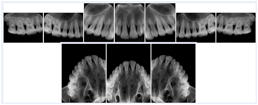

Intra-oral radiography typically involves acquisition of multiple images of various parts of the dentition. Many digital radiographic systems offer customized templates that are used for displaying the images in a study on the screen. These templates may also be referred to as mounts or view sets. The Structured Display Object represents a standard method of encoding and exchanging the layout and intended display of Structured Displays. A structured display object created in this manner could be stored with a study and exchanged with images to allow for complete reproduction of the original exam.

1. A patient visits a General Dentist where a Full Mouth Series Exam with 18 images is acquired. The dentist observes severe bone loss and refers the patient to a Periodontist. The 18 images from the Full Mouth Series along with a Structured Display are copied to a DICOM Interchange CD and sent with the patient to see the specialist. The Periodontist uses the CD to open the exam in his Dental Radiographic Software and consults via phone with the General Dentist. Both are able to observe the same exam showing the images on each user's display using the exact same layout.

Intra-oral Full Mouth Series Structured Display

Figure OO-1. Intra-oral Full Mouth Series Structured Display